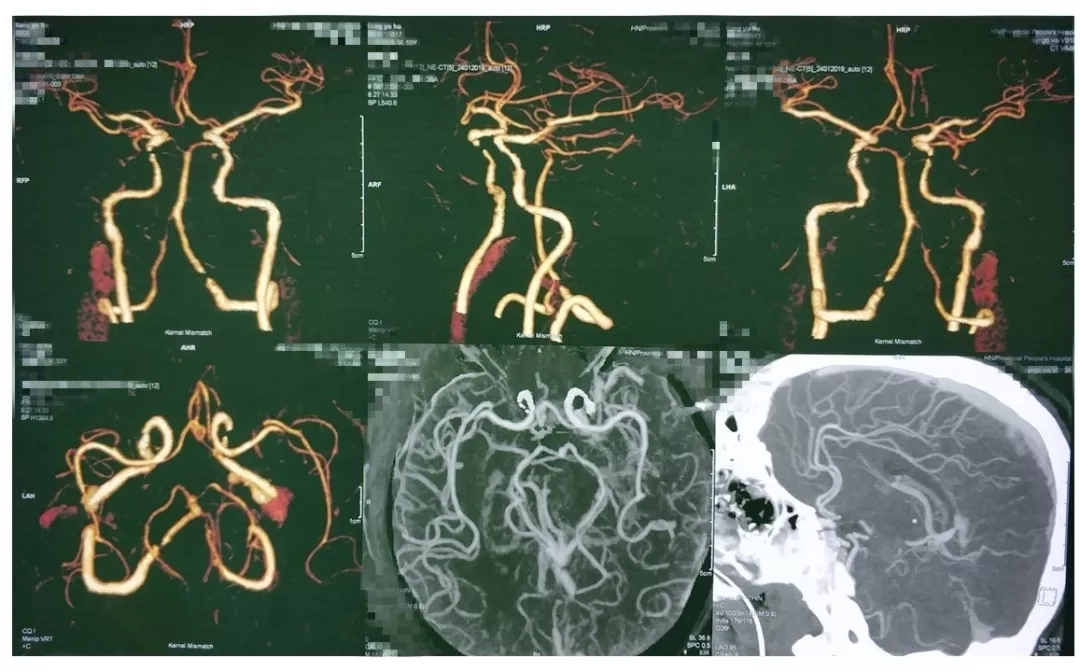

入院后完善CTA,DSA等检查提示颅内多发动脉瘤:

其中右侧颈内动脉眼段动脉瘤(约13.8*14mm大小,瘤颈8.04mm)。和家属沟通病情,告知介入和开颅手术两种治疗方式的风险利弊后,患者家属选择开颅右侧眼动脉段动脉瘤夹闭手术治疗。

进一步行DSA+CT融合,模拟手术入路视角。

手术采取复合手术条件下磨除前床突,利用Scepter球囊封堵瘤颈,阻断瘤内供血后行动脉瘤夹闭。